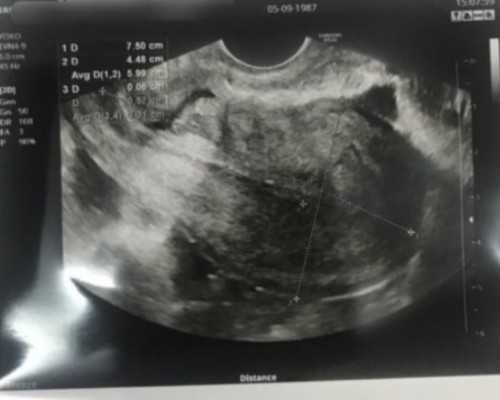

此外,还开展了阴超声监测排卵、阴超声引导下输卵管通液、人工授精等操作技术。同时,致力于预测卵巢早衰、早期诊断和生育功能;恢复肥胖性闭经(多囊卵巢)排卵功能;治疗罕见疾病,如性早熟、性发育延迟和性别异常。对子宫内膜异位症、复发性流产(习惯性流产)的早期诊断和治疗有独特的见解,并取得了良好的治疗效果。